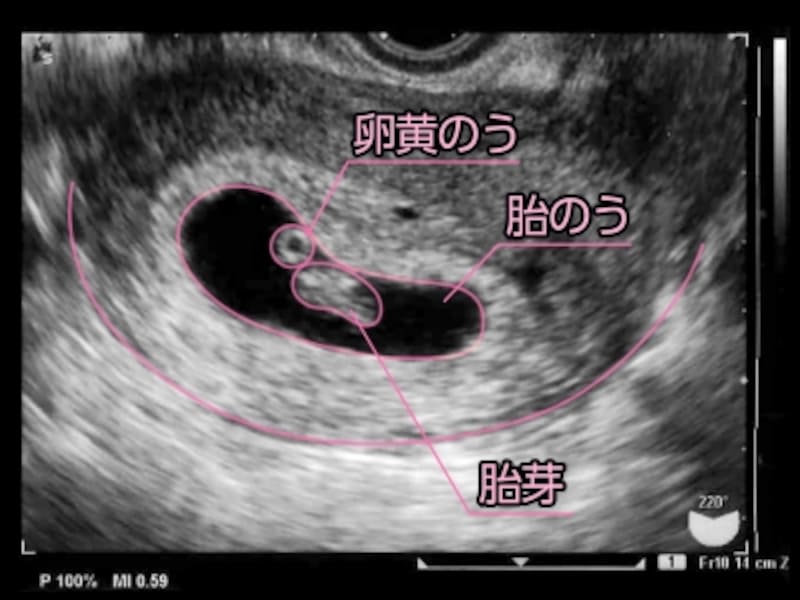

心拍無事確認 しかし新たな問題が Nekomanma

小さいけど心拍確認 助産師さきの不妊治療で年子 0才 2才 育児

いざ 心拍確認 いぶのブログ

妊娠6週目 エコー写真 胎芽や胎嚢大きさ 心拍確認や気になる流産 妊娠初期 All About

妊娠7週目 胎芽 胎嚢のエコー写真や大きさ つわりや流産 妊娠初期 All About